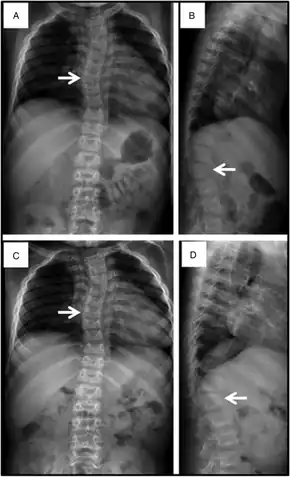

The most severe cases of Sly syndrome can result in hydrops fetalis, which results in fetal death or death soon after birth. Some people with Sly syndrome may begin to have symptoms in early childhood. Symptoms can include an enlarged head, fluid buildup in the brain, coarse facial features, enlarged tongue, enlarged liver, enlarged spleen, problems with the heart valves, and abdominal hernias. People with Sly syndrome may also suffer from sleep apnea, frequent lung infections, and problems with vision secondary to cloudy corneas. Sly syndrome causes various musculoskeletal abnormalities that worsen with age. These can include short stature, joint deformities, dysostosis multiplex, spinal stenosis, and carpal tunnel syndrome.[1]